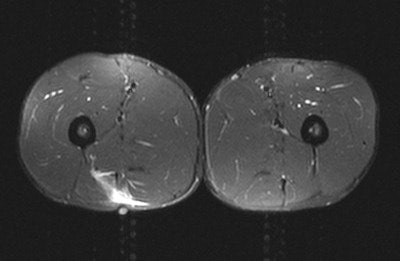

"Existe gran debate acerca de cuando es mejor obtener imágenes de lesiones en los tejidos blandos. El atleta lo desea inmediatamente o al menos dentro de las 24 horas. En mi experiencia, es mejor esperar unas 24 a 48 horas ya que de otra manera existe el riesgo de obtener un falso negativo," afirmo Healy, quien ayuda a cuidar a los atletas de varios clubes de football de Primera Liga y Liga de Campeones, así como también de equipos de rugby de Primera Liga, y quien ha estado involucrado en un estudio de lesiones de pierna-muslo de la Liga de Campeones desde 2007. "Si la imagen no correlaciona con los hallazgos clínicos, es entonces muy importante repetir la imagen. A menudo, si se obtiene la imagen muy temprano, se pierde la medida de lo que está sucediendo."

El Dr. Healy tiene una regla simple para determinar que modalidad debe usarse: si el paciente señala la anormalidad con un dedo, se debe empezar con ultrasonido; pero si el paciente la señala con la mano, se debe ir directamente a una imagen por RM. Además, el ultrasonido es mejor para obtener imágenes de estructuras superficiales, mientras que la RM es mejor para estructuras profundas.

Aun si el diagnóstico clínico es obvio, la obtención de imágenes se requiere para medir la extensión de la lesión y para identificar cualquier complicación. Si ha ocurrido una lesión significativa, la imagen es necesaria para asegurarse de que el diagnóstico inicial era correcto, afirmó Healy. Finalmente, las imágenes pueden ser benéficas para documentar la existencia, progresión o resolución de una enfermedad, lo cual puede ser útil por razones medico-legales.